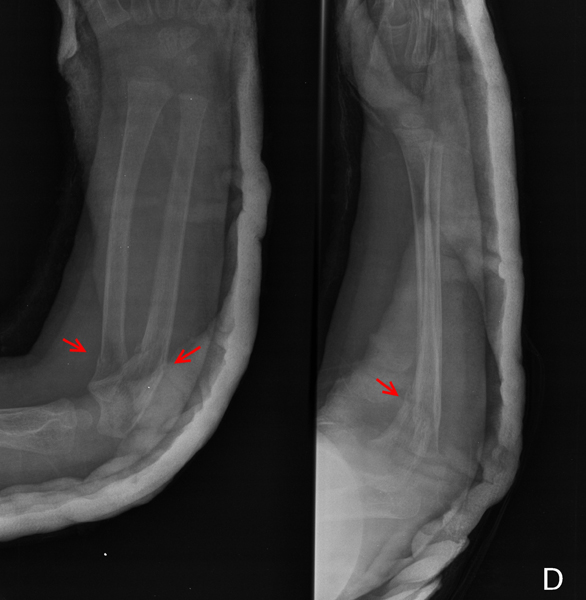

El diagnóstico prenatal se realiza por ultrasonografía en los tipos II y III, apreciándose fracturas prenatales y aumento de la translucencia. Las fracturas pueden detectarse desde las 14 semanas de embarazo en el tipo II y desde la semana 18 en el tipo III. (

Figuras 3 y

Figura 4). Las múltiples fracturas producen deformidad de huesos largos, costillas y cráneo. En el tipo IV ocasionalmente se realiza el diagnóstico sobre la semana 22 por acortamiento de huesos largos, sin fracturas ni osteopenia. La OI tipo I no se puede diagnosticar

Figura 3. Fractura de radio y cúbito (flechas).

Figura 4. Fractura distal de tibia (flecha) en el mismo paciente afecto

de osteogenesis imperfecta tipo 1.